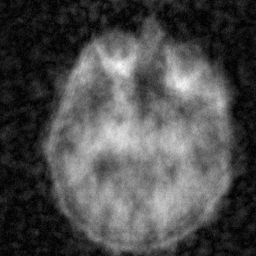

Multi-modality (or multi-channel) imaging is becoming increasingly important and more widely available, e.g. hyperspectral imaging in remote sensing, spectral CT in material sciences as well as multi-contrast MRI and PET-MR in medicine. Research in the last decades resulted in a plethora of mathematical methods to combine data from several modalities. State-of-the-art methods, often formulated as variational regularization, have shown to significantly improve image reconstruction both quantitatively and qualitatively. Almost all of these models rely on the assumption that the modalities are perfectly registered, which is not the case in most real world applications. We propose a variational framework which jointly performs reconstruction and registration, thereby overcoming this hurdle. Numerical results on simulated and real data show the potential of the proposed strategy for various applications in multi-contrast MRI, PET-MR, and hyperspectral imaging: typical misalignments between modalities such as rotations, translations, zooms can be effectively corrected during the reconstruction process. Therefore the proposed framework allows the robust exploitation of shared information across multiple modalities under real conditions.